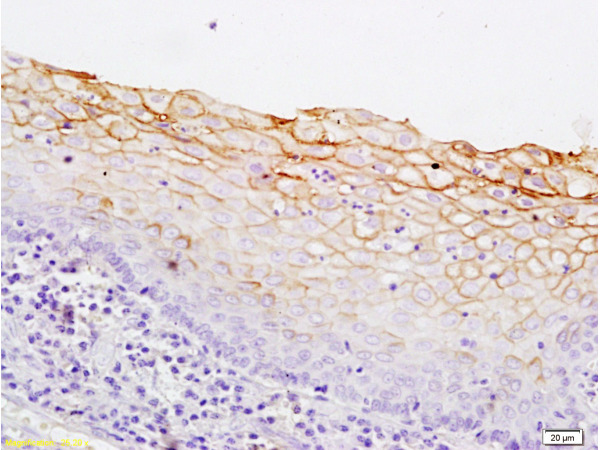

Cytokeratin 5 Polyclonal Antibody

Product Name Cytokeratin 5 Polyclonal Antibody